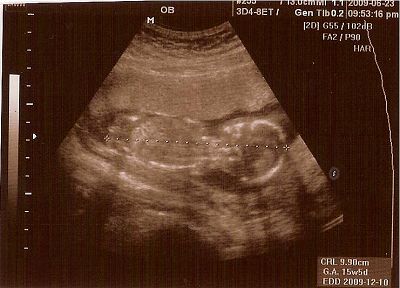

12W2D醫生安排照頸部透明帶

老愛趴著的娃娃,讓我只得在醫院長長的走廊來回不停地走

一直不斷跟他溝通快快轉過來

好不容易可以照了

醫生帶著我數著娃娃的手指頭,1、2、3、4、5

看看四肢、心臟 、屁屁等器官

看著娃娃揮舞著四肢可愛的模樣,好感動好感動

隨著時間的經過,大概也有三十分鐘了吧!

醫生左搖右晃地還沒結束

心中正納悶著

結果醫生說鼻骨好像不是很清楚

有百分之六十的唐寶寶有這個情況

頓時,心都涼了一截

在醫生的說明下,叫我別太擔心,因為還要看抽血及整體的評估報告

拿了超音波照片的我,帶著一顆忐忑不安的心離開醫院